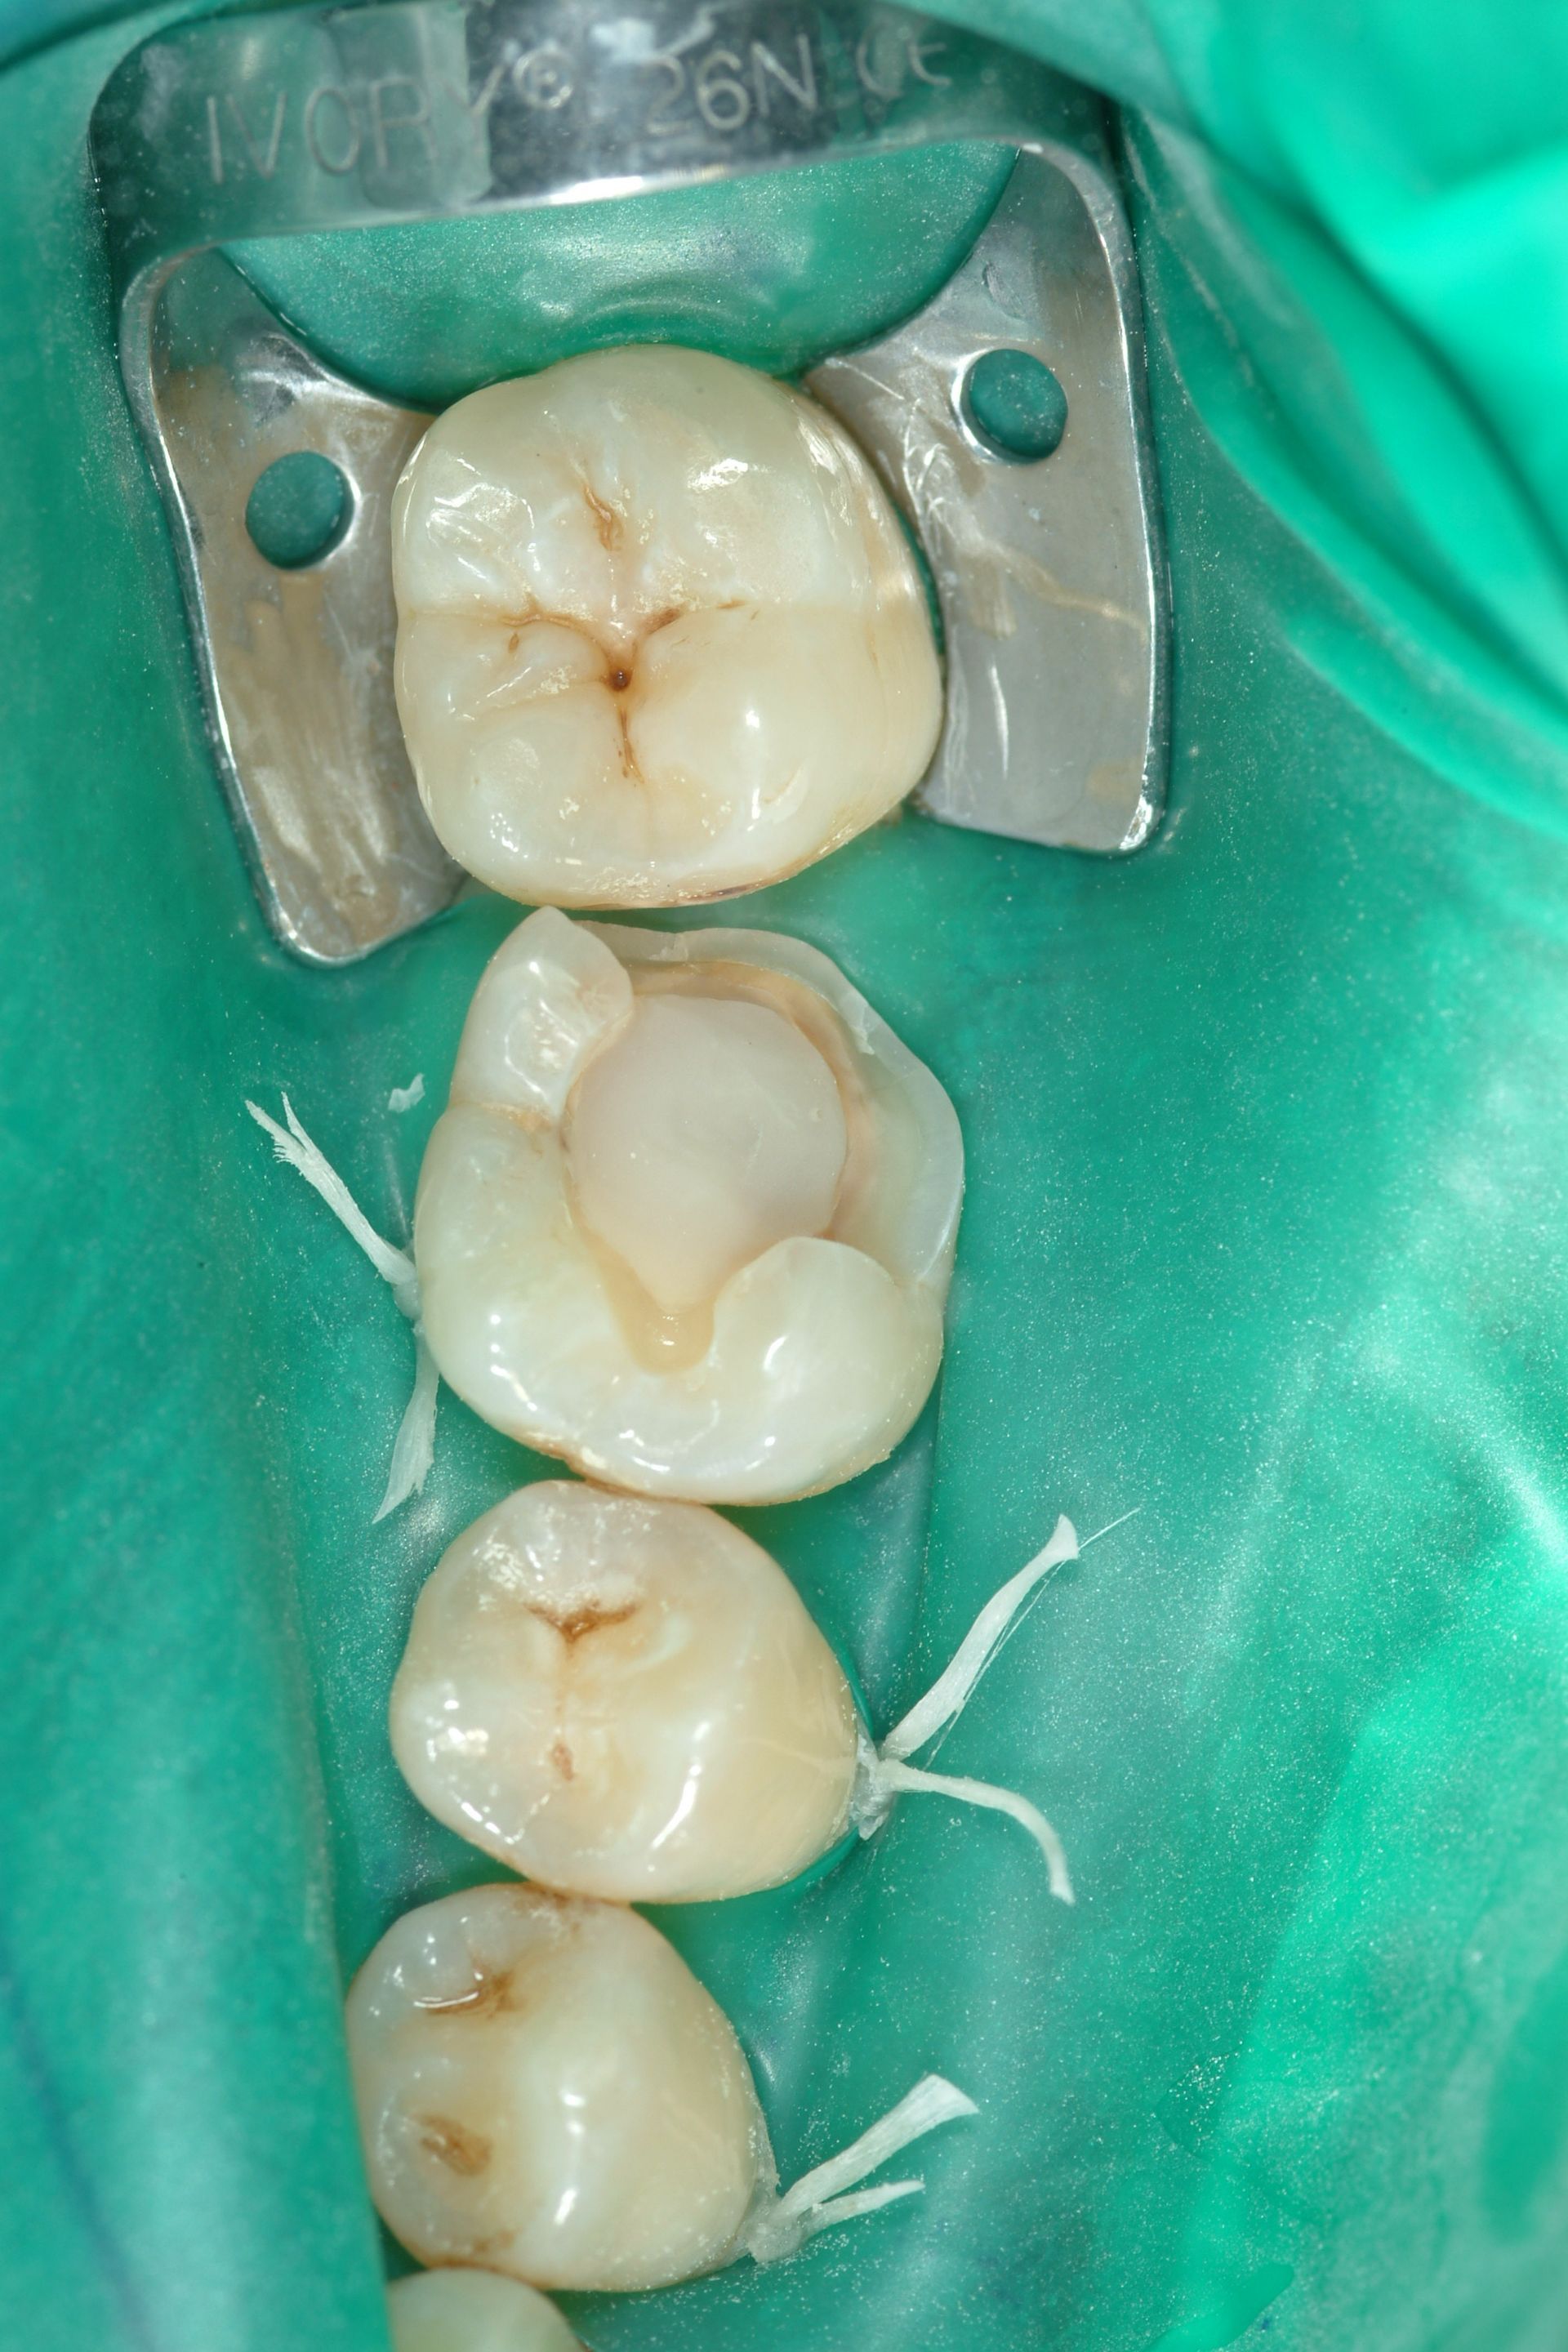

Conservativa indiretta

Lo specialista effettua interventi di conservativa indiretta, inclusa la sostituzione delle vecchie amalgame con restauri in composito. Questa tecnica permette di rimuovere le carie e riparare i denti danneggiati, utilizzando materiali estetici e biocompatibili che si integrano perfettamente con il dente naturale.